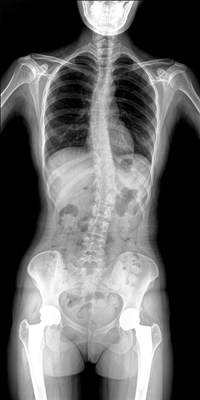

臨床需要對患者的脊柱情況有全面了解,故而術前術后均需要均需要借助DR拍攝X光片便于分析病情、明確診斷及術后觀察治療效果。大視野動態(tài)DR可以對患者的脊柱進行長尺寸攝影,一次拍攝就能獲取完整的脊柱全景圖像。診斷醫(yī)生通過拍攝后的影像測量全脊柱的生物角度、Cobb角等,為脊柱側彎的畸形矯正患者術前術后的檢查提供重要的診斷依據(jù)。

通過大視野動態(tài)DR進行全脊柱攝片,其得到的影像密度均勻、清晰、接緣處過渡自然。且操作更加便捷,不需要二次攝片然后進行圖像拼接,拍攝時間短,效率高。在減少輻射劑量的同時也能為臨床醫(yī)生帶來更精確的診斷信息。非拼接影像可保證雙腿測量(如力線)數(shù)據(jù)的準確性,有效避免攝影信息的丟失。給手術醫(yī)生提供準確的術前診斷數(shù)據(jù),提高手術成功率。

綜上所述,大視野動態(tài)DR進行全脊柱成像能夠清晰的呈現(xiàn)骨關節(jié)結構,可以在全景脊柱圖像基礎上對角度值進行測量,能夠很好的反映骨骼的真實比例與長度,為臨床診斷和治療提供了更精確的數(shù)據(jù),有著重要臨床應用價值。